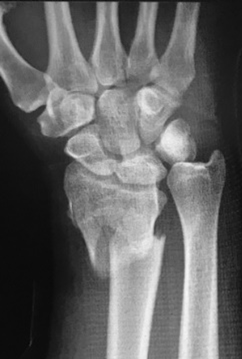

![]() |

| Both bone forearm fracture | Monteggia fracture-dislocation | Galeazzi fracture-dislocation |

- Galeazzi fracture: Distal ⅓ radial shaft fracture with associated distal radio-ulnar joint (DRUJ) dislocation